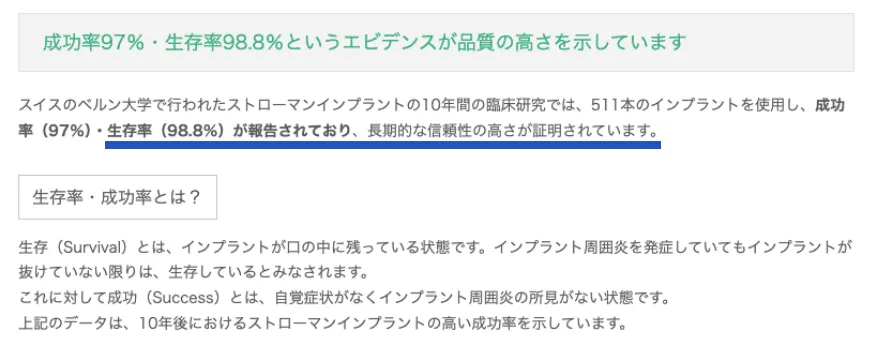

保険適用のブリッジと比較しても、3倍の確率で長持ちします。

ストローマン社のインプラントが

10年後も使える確率は98.8%

引用元:https://straumannpartners.jp/medical/reason/trust/

※インプラントを入れたその日からすぐに歯を入れて食事できる治療法でのデータです